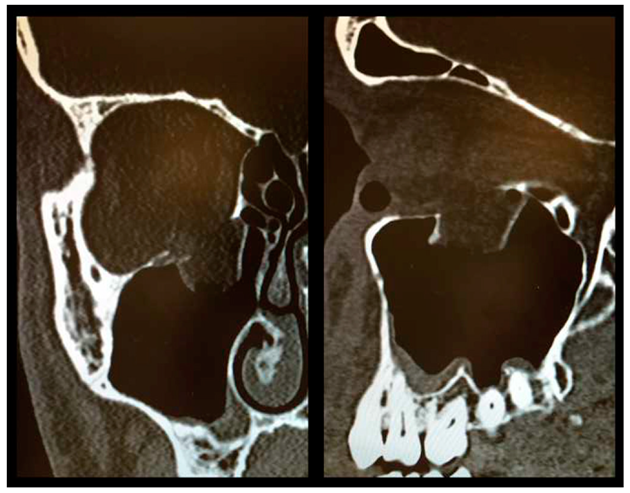

As described above, all patients underwent a first ophthalmologic examination on the day of admission. Following the decline of the frequently present periorbital swelling, all patients had a detailed orthoptic assessment preoperatively. The mean time elapsed from injury to the detailed orthoptic assessment was 1.93 days (SD = 1.45; range: 0–7 days). The mean time between the day of injury and the surgical repair using Ethisorb® patches was 4.33 days (SD = 2.71; range: 0–13 days). A representative example of a typical case is illustrated in Figure 2 and Figure 3 showing both the pre- and postoperative CT scans.

Figure 2.

Preoperative CT scan showing a large OFF ((left) coronal view, (right) sagittal view).